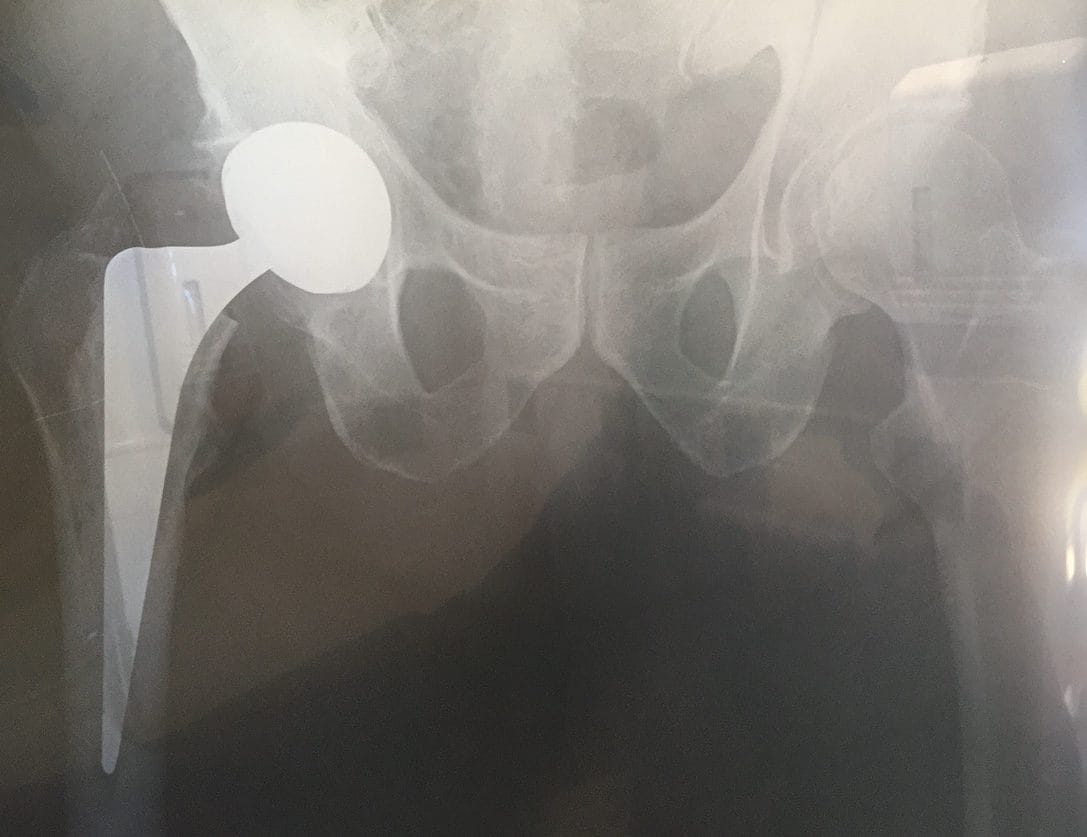

A week or so later, I received a report from Sir John’s trainee. The operation had been a success. Should any follow-up be needed, one of Sir John’s former trainees was practicing in Sydney—Dr. Bruce Shepherd. In the UK, Bruce had become interested in Charnley’s total hip arthroplasty. Back in Sydney, he quickly established himself as a specialist in this operation.

Bruce was influential in many orthopedic and other medical associations—such as the Australian Society of Orthopaedic Surgeons, the Council of Procedural Specialists, and the Royal Australasian College of Surgeons. In about 1992, Mr. C. needed revision of his surgery, and this was performed successfully by Bruce.

My story now advances through some three decades, well past Bruce’s and Desmond’s retirements and deaths, to June this year. Within a week of having an ache in my groin, my hip collapsed. Now it was my turn to benefit from John Charnley’s expertise. Michael promptly operated on me and my hip is back to normal. It completes my little circuit of personal experience of hip surgery, from Australia, Italy, England, and South Africa, and back to Australia.